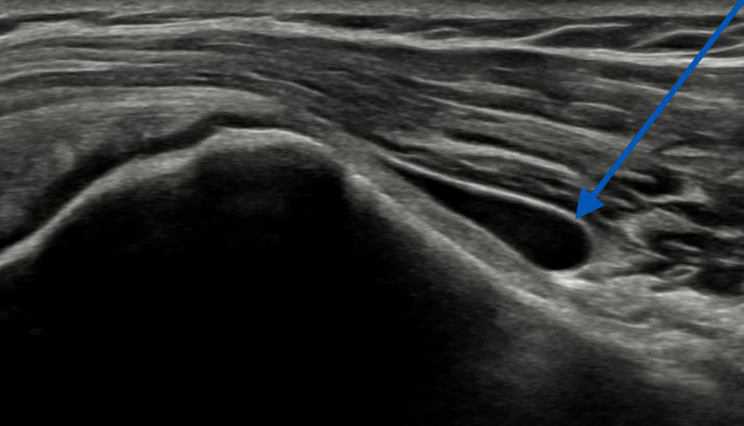

Bij PijnMC kunnen wij uw pijnklachten verminderen door een echografische ingrepen uit te voeren.

Er zijn diverse echogeleide ingrepen die wij afhankelijk van uw specifieke klachten kunnen bieden. Lees meer